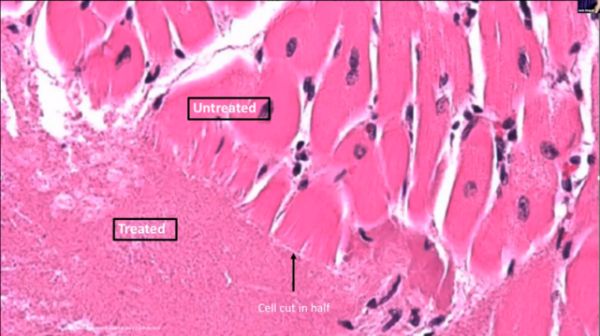

左下角被液化的组织与非治疗区之间有明显的分界

虽然较热机制的超声治疗起步晚,但是组织剥离方法也有其自身的优点:(a)不受热机制中常见的热池效应(heat-sink)的影响,可以治疗血管周围的组织,应用范围更广;(b)组织剥离的损伤是空化机械作用的结果,可以防止热扩散而影响健康组织;(c)组织毁损方法中产生的空化云,沸腾气泡等更便于超声设备的监控,利于治疗过程的把控。(d)组织剥离将目标组织粉碎,治疗期间不会产生热凝固损伤,可以形成组织可吸收的液体,更适于临床应用;(e)组织剥离方法对较大的病变组织可以围绕肿瘤组织进行连续治疗,将肿瘤组织从健康组织中切割出来,大大提高治疗效率。